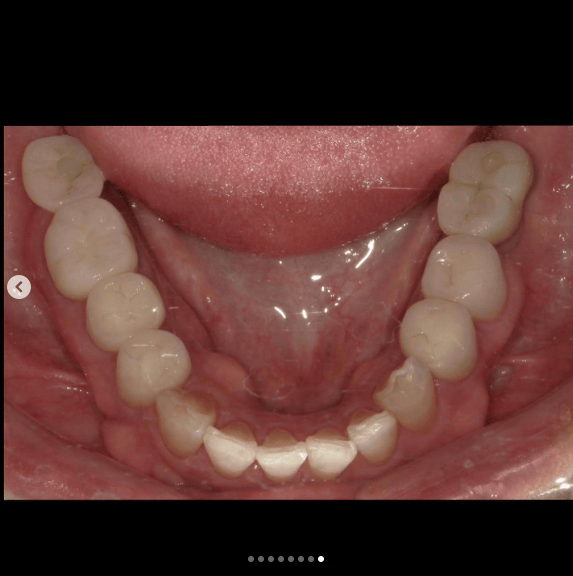

噛み合わせから審美的なところまで、トータルで治療させて頂いた患者様です。

ここまでやるとなると、できないクリニックもありますし、できるところでも年単位でかかってしまうクリニックが大半だと思いますが、今回は4月末にカウンセリングでご来院いただき、5月に治療をスタートして9月末には診療が終わっています。

治療回数や、治療期間がかかってしまうと、患者様も通院が辛くなったり疲れてしまったりしてしまうと思います。どんどん綺麗になっていく、食事がしやすくなっていくという実感がある方が患者様に楽しく治療に臨んでいただけると思うので、私は診療のスピード感を大切にしています。

トータルでやらせていただいたので、噛み合わせなどの機能面から外見などの審美性もかなり良くなり、患者様にも満足して頂けてよかったです。

治療期間 約4ヶ月